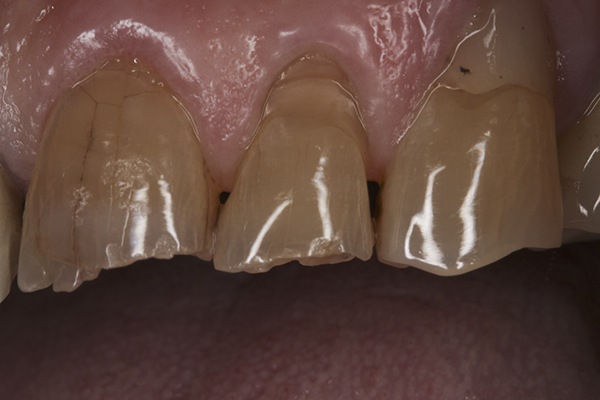

(10.) Preoperative anterior, closed view. Note the end-to-end occlusion of the anterior teeth and the wear on the incisors and centrals resulting in no anterior or canine guidance.

Figure 10

(13.) Preoperative anterior, close-up view.

Figure 13